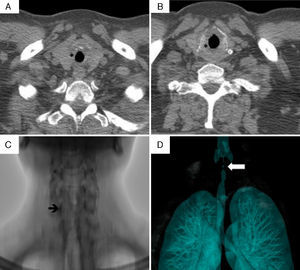

A 17-year-old woman had been diagnosed as having GPA at the age of 11 on the basis of pulmonary and renal involvement. Eighty-four months after the diagnosis of GPA, she presented with a 2-month history of dysphonia, laryngeal stridor, dry cough and dyspnea, and a BVAS score of 3. Computed tomography revealed tracheal stenosis measuring 6cm in length, and a transverse diameter at the narrowest portion of 5mm. Tracheostomy was performed due to airway compromise and, after 2 months of follow-up, decannulation remained impossible.